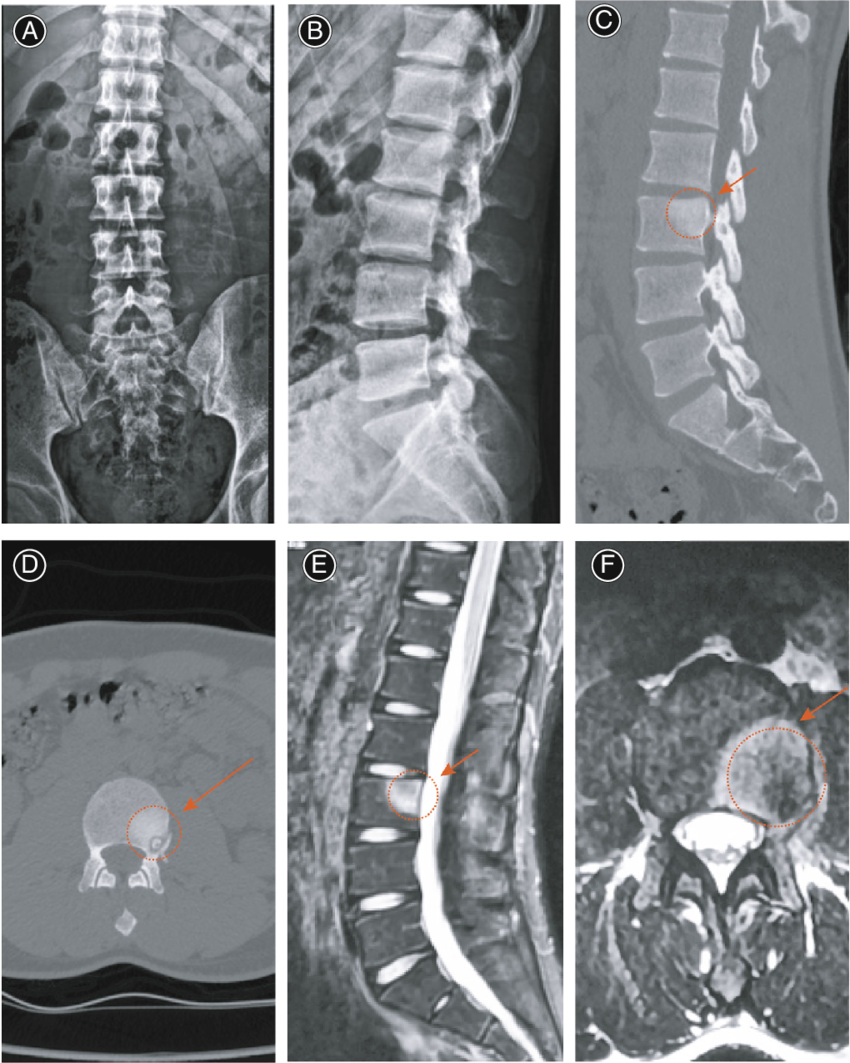

Diagnostika:

- UZI va rentgen tekshiruvi

- MRT (to‘qimalar holatini aniqlash uchun)